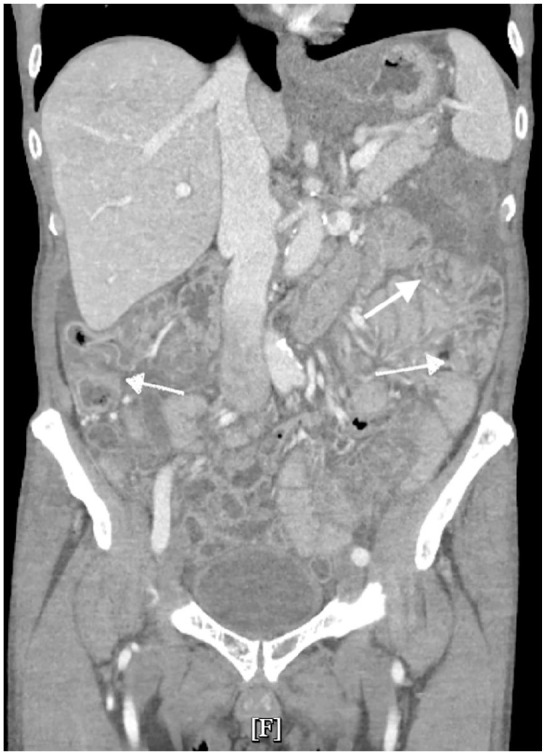

Immunotherapy-induced pseudomembranous colitis (PMC) is an uncommon but increasingly recognized adverse effect of immune checkpoint inhibitors, particularly in patients with advanced malignancies. We present a case of a 68-year-old male with gastric adenocarcinoma undergoing treatment with immunotherapy and chemotherapy, who developed symptoms of PMC. Workup for Clostridium difficile and other common etiologies was negative. Colonoscopy revealed severe mucosal congestion and yellowish-green exudates, consistent with PMC. Based on the biopsy results and clinical presentation, after excluding common etiologies, immunotherapy-induced PMC was suspected. The patient responded to steroid therapy, with gradual improvement and a tapering regimen upon discharge. This case underscores the diagnostic challenges in identifying the etiology of PMC, particularly when it presents with diffuse involvement of the colon, which is an uncommon presentation for immunotherapy-related colitis. The overlap in clinical, endoscopic, and histopathological findings with other forms of colitis, such as Clostridium difficile infection (CDI) and inflammatory bowel disease, highlights the need for heightened awareness among clinicians. This case highlights the diagnostic challenges in recognizing immunotherapy-induced PMC, particularly with atypical, diffuse colonic involvement. The overlapping features with other colitis make timely diagnosis difficult. Further research is needed to refine diagnostic criteria and management strategies for immunotherapy induced colitis (IMC).

Abstract Image